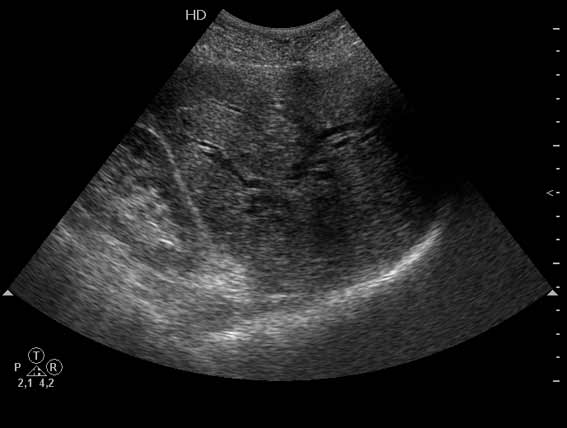

Очень пожилая женщина, обратилась в стационар из-за появления желтухи. Периодически беспокоили боли в эпигастрии и правом подреберье.

Желчный пузырь удален по поводу ЖКБ лет двадцать назад.

Не могу сказать что я вижу камень в холедохе на представленных сонограммах. Холедох расширен; интра-печёночные жёлчные пути тоже (значит прошло > 3 недель от момента обструкции). Жалоб на сильные приступообразные боли я не прочёл. Всё таки буду думать сначала о опухоли (если при УЗИ не нашли камня); рекомендация-таргетное КТ печени и поджелудочной.

Дело в том, что в холедохе имеется нечто изоэхогенное (не знаю, видно ли это нечто на ваших мониторах). Врач УЗИ при осмотре перед поступлением в стационар на основании этой картины в заключении отметил возможность опухоли холедоха.

Гнойный холангит на фоне обструкции БДС конкрементом (камень вне скана). В холедохе определяется желчь с осадком, которая может быть ошибочно принята за его опухоль.